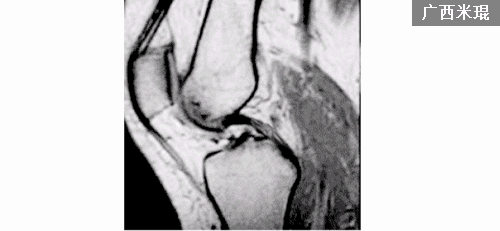

1.韧带实质部撕裂 (根据表现分为3级)

2.后交叉韧带股骨附丽点撕脱(不多见)

后交叉韧带损伤的MRI分级:

Grade1:韧带内损伤,无长度改变。

Grade2:韧带内损伤并长度延长。

Grade3:完全性韧带撕裂。